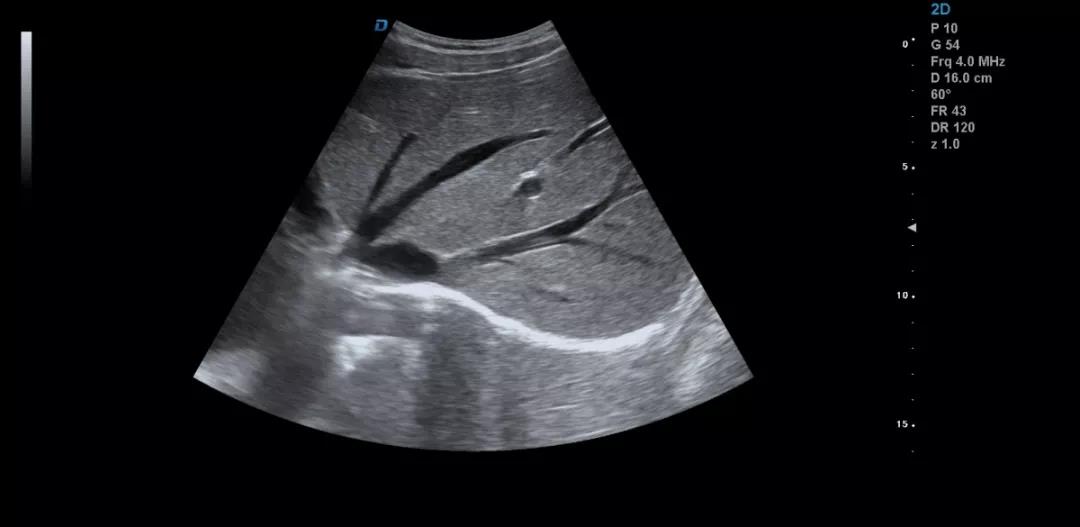

眾所周知,肝臟有很多檢查死角,成為超聲檢查的盲區(qū),如肺和骨所掩蓋處,肝右前上段及右后上段的膈頂部,左外葉外側(cè)角區(qū),沿肝臟表面的肋骨下區(qū)等等部位,只有極其細(xì)致的檢查配上精巧的手法才能盡可能的顯示清楚這些部位。

如果我們能夠細(xì)致的檢查每個病人,所謂的肝臟死角能夠盡可能的探測到,肝臟的死角其實(shí)只有膈頂部,其他的部位如果能細(xì)致檢查都可以探測到。

發(fā)現(xiàn)肝臟病變時要多切面多角度掃查,可以了解病變的解剖位置并排除假陽性。